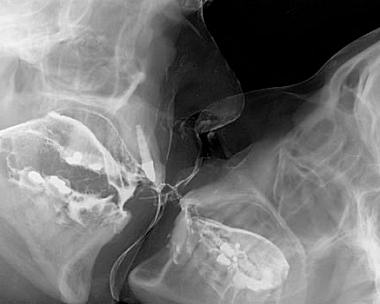

Senhoras e senhores, apresento-lhes a anatomia de um beijo !!!

Uma tomada radiográfica do momento que, se não é o principal do amor entre um casal, com certeza é o mais praticado, e responsável direto por se abrirem as portas da felicidade !!!

E com direito a canal tratado, um implante dental e muitos e muitos amálgamas.Se enxergássemos assim a boca de quem se flerta, com certeza, se beijaria beeeeeeem menos !!! 😀

Muuito legal! O implante ali é o melhor kkkkkkkk